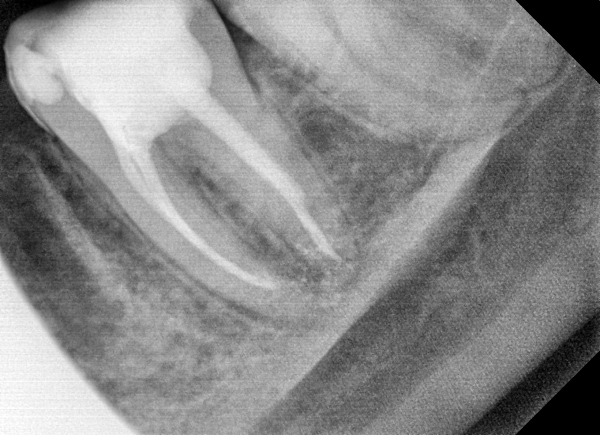

Месяц назад мне начали лечить очень воспаленный зуб, седьмой нижний слева. После пломбировки каналов наложили временную пломбу. После наркоза зуб болел при накусывании 2 недели, потом боль начала стихать и на сегодняшний день зуб не болит. При постукивании по зубу, я обратил внимание, что боль идет со стороны щеки. Сделав снимок увидел, что канал слева не запломбирован до конца. Врачи говорят, что все в порядке. Я начал интересоваться этим вопросом по причине боязни потерять этот зуб, на который будет крепиться мостовидный протез.

Есть ли воспаление в канале?